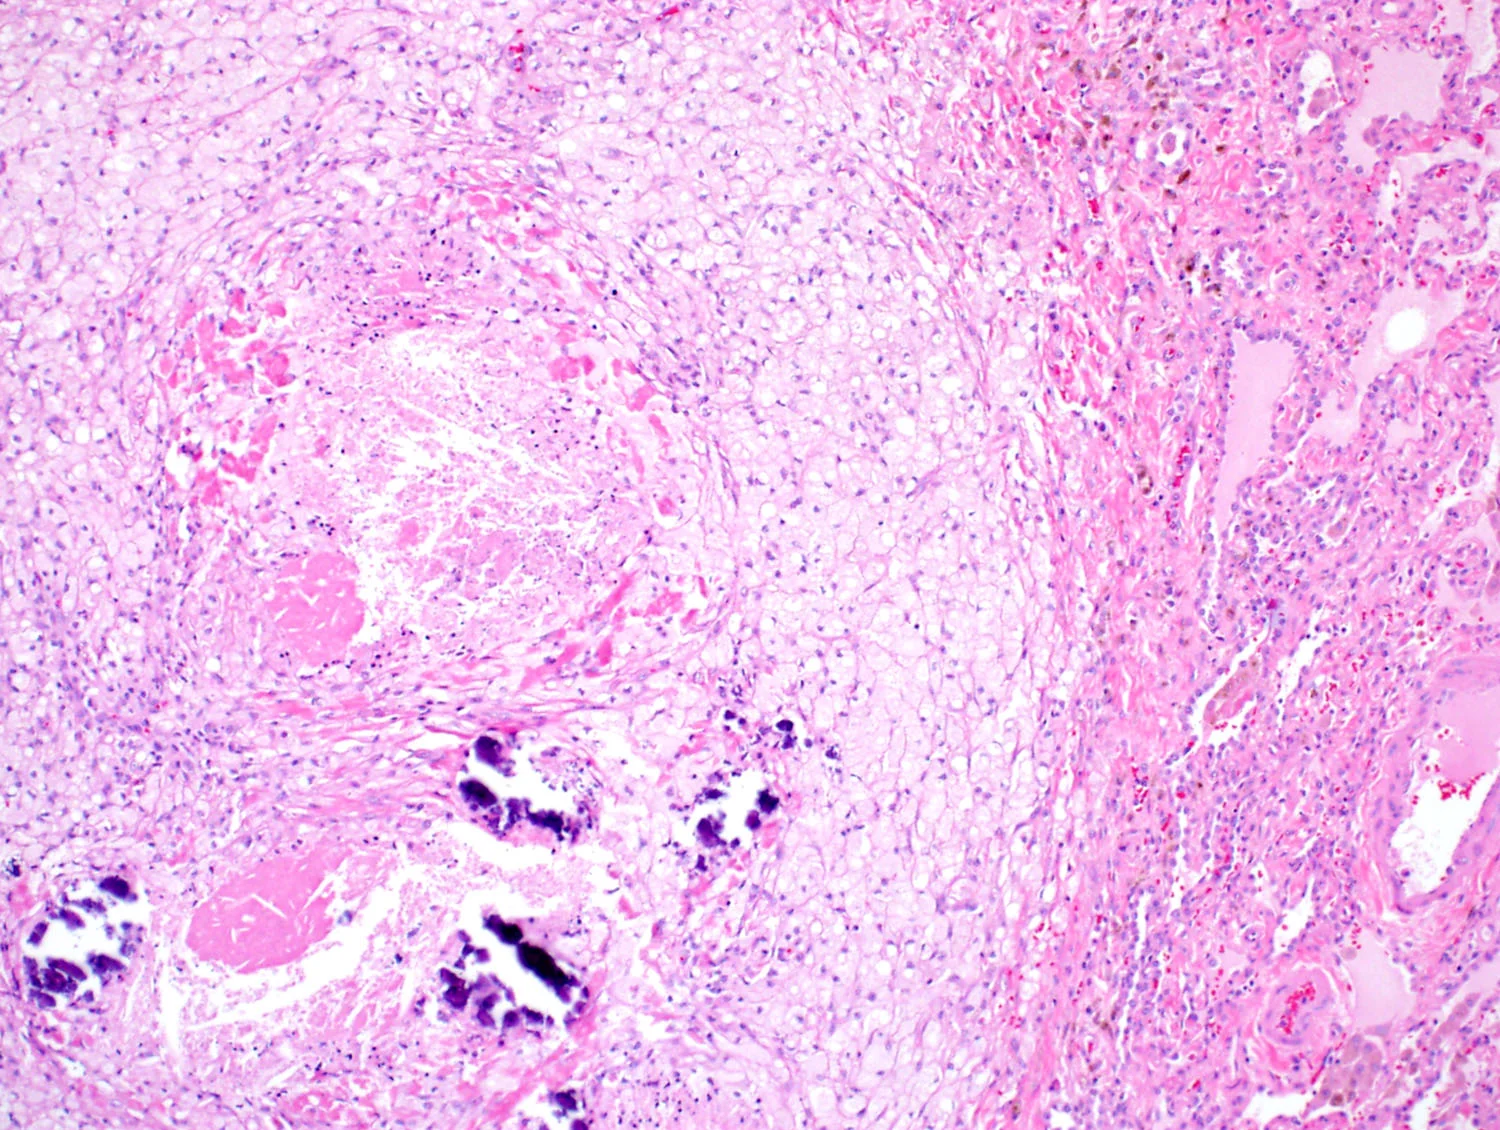

Fibrosis w/ Granulomas

Fibrosing Interstitial pneumonia with granulomas (see comment).

Comment: The biopsy shows advanced fibrosis with architectural distortion and scattered (necrotizing or nonnecrotizing) granulomas. The differential diagnosis includes chronic hypersensitivity pneumonitis, sarcoidosis/berylliosis, chronic infection, and chronic aspiration. Because of the presence of granulomas in this case, usual interstitial pneumonia of idiopathic pulmonary fibrosis is not favored. The diagnosis of ILD requires a multidisciplinary approach. Correlation with imaging studies and clinical history is suggested.